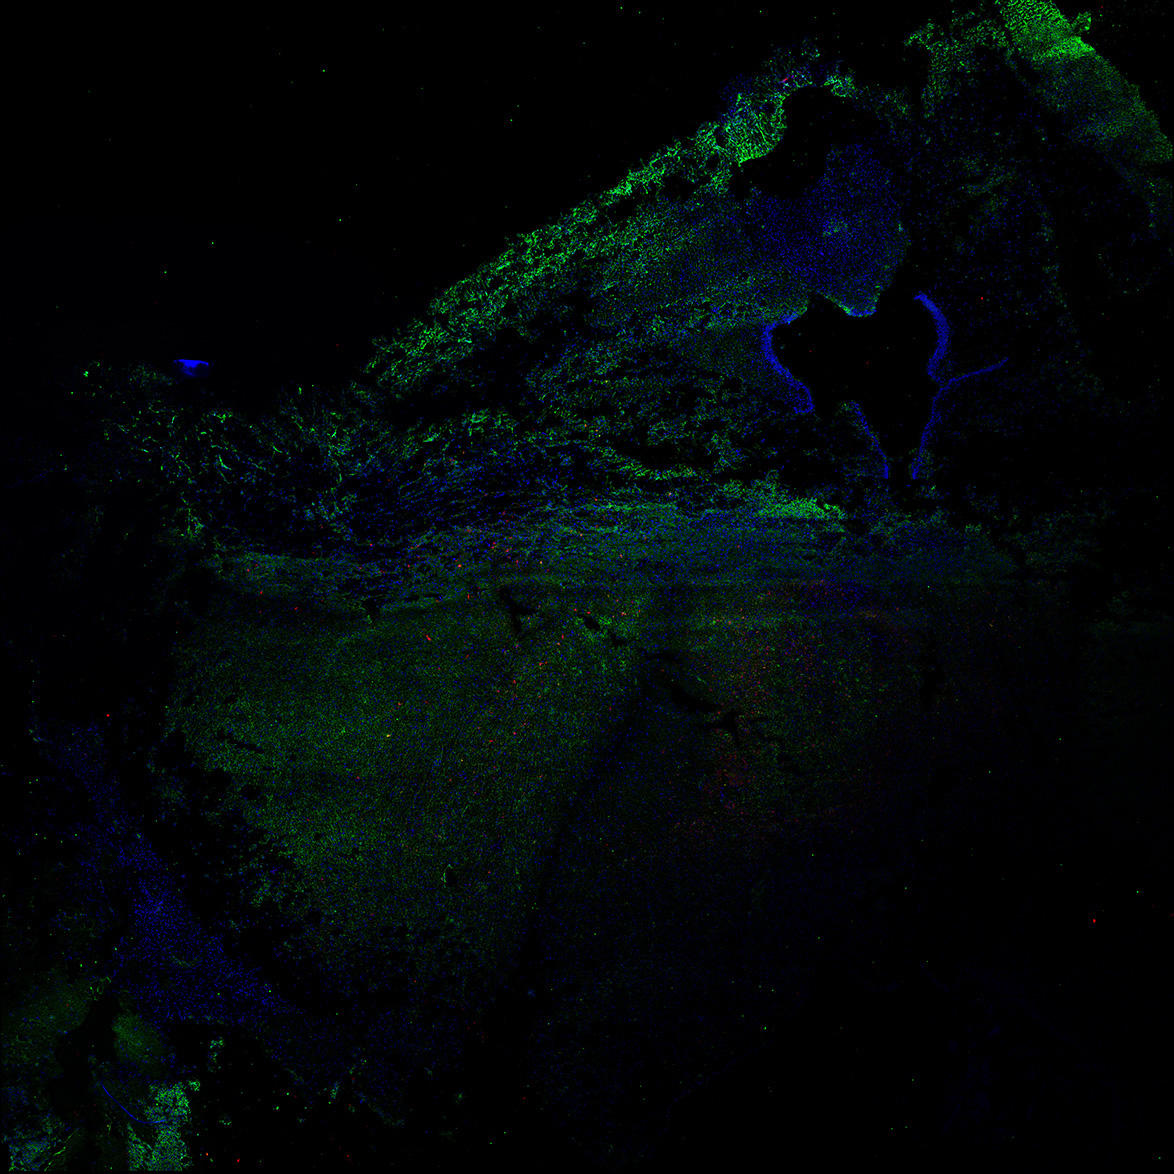

DAPI

11PCW human midbrain

MAP2

TH

Merged